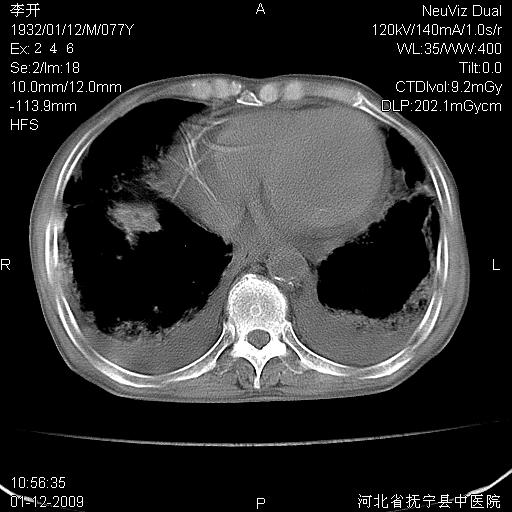

以下是引用黑白光影在2009-1-19 16:49:00的发言:[br]心衰肺水肿;心包、胸腔积液;冠脉钙化;肺部感染。